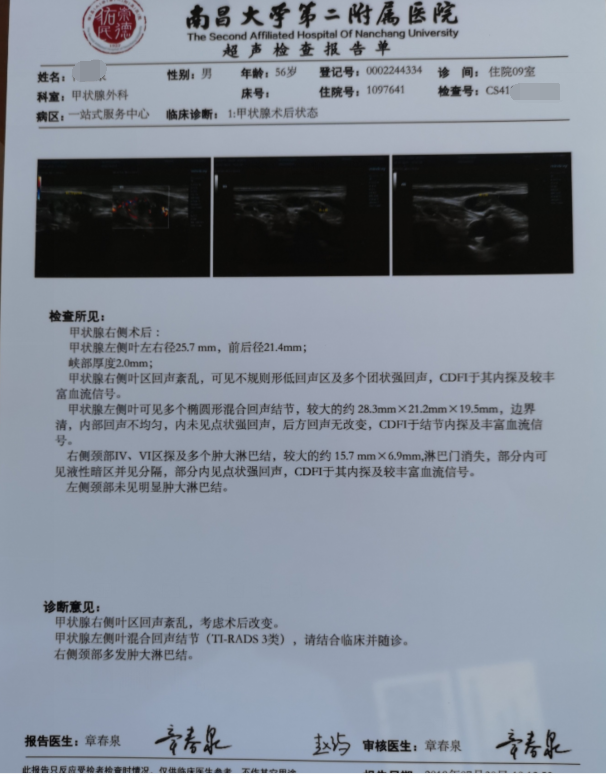

甲状腺癌再次手术

病例2 右2,右4R区,左6区残留,颈部切口清扫,未开胸